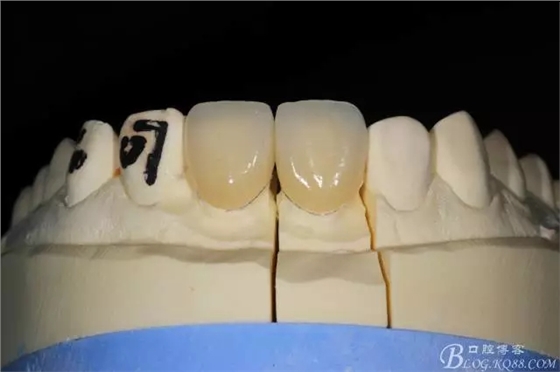

模型上制做完成

試戴